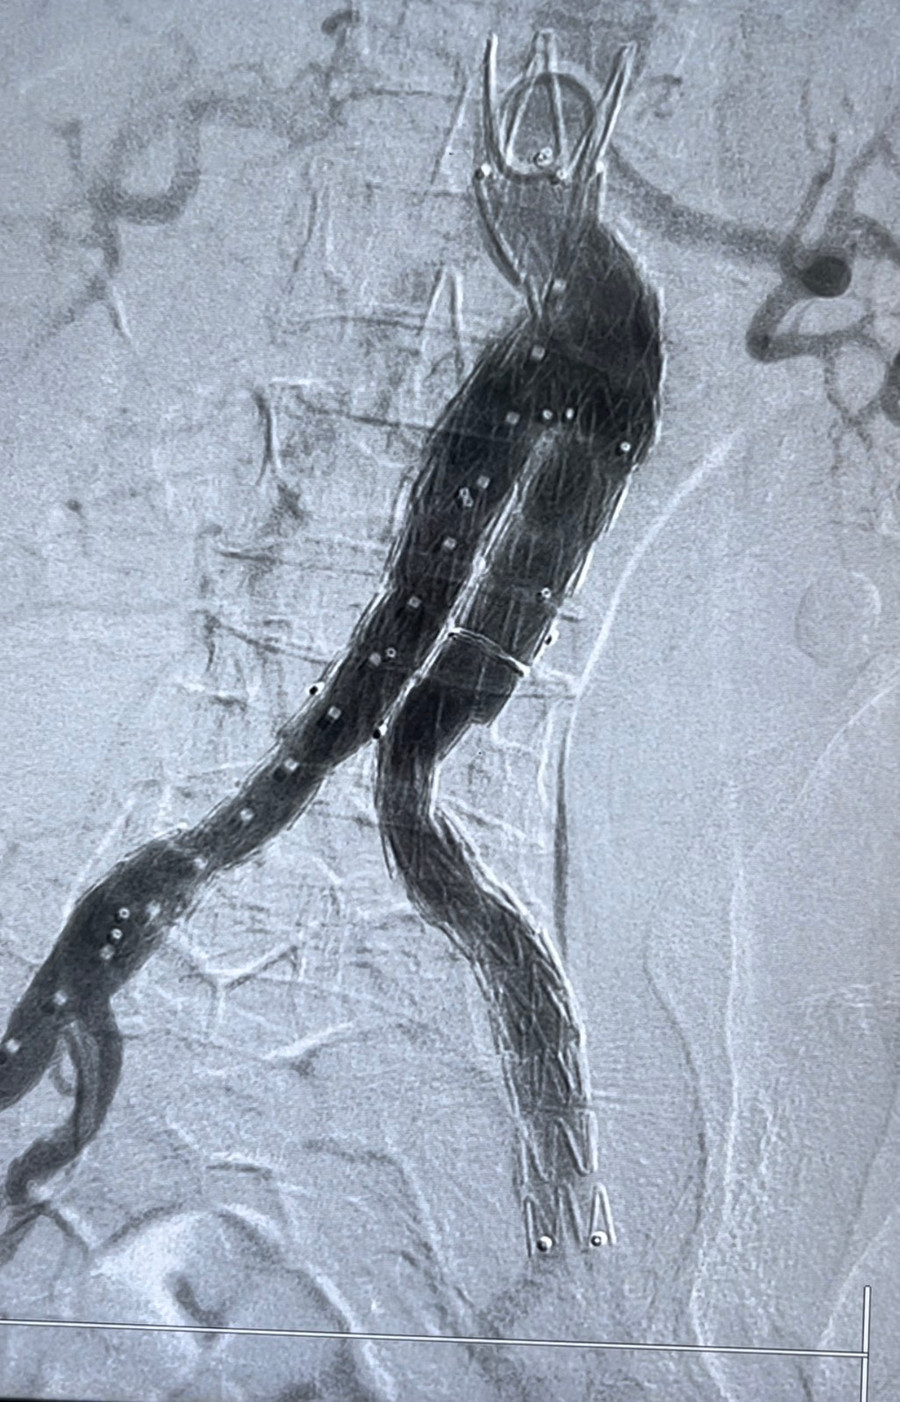

Ngay lập tức, trong tối cùng ngày, bệnh nhân được chuyển tới Trung tâm Can thiệp tim mạch. TS. Hồ Anh Bình – Trưởng kíp can thiệp cùng ekip can thiệp tim mạch đã tiến hành can thiệp cấp cứu thành công, đặt stentraft động mạch chủ bụng bít hoàn toàn túi phình lớn động mạch chủ bụng.

![]() |

| Ê kíp can thiệp tim mạch đã cấp cứu thành công, đặt stentraft động mạch chủ bụng, bít hoàn toàn túi phình lớn động mạch chủ bụng. |